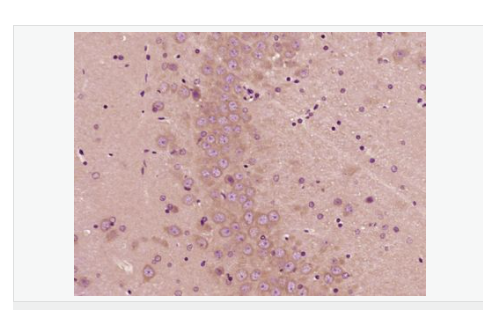

產(chǎn)品介紹PBR (Peripheral type Benzodiazepine Receptor) is a ubiquitous protein (18 kDa) found in most steroidogenic tissues. It is located primarily in the outer mitochondrial membrane of steroid producing tissues and is found in association with a 34 kDa voltage dependent anion channel protein (VDAC). PBR interacts with some benzodiazepines and has different affinities than its endogenous counterpart. PBR appears to be a key factor in the transport of cholesterol from the outer to the inner mitochondrial membrane to permit the initiation of steroid hormone synthesis. It is thought to be part of the mitochondrial permeability transition pore (PT) and to be involved in apoptosis. It is speculated that patients with congenital lipoid adrenal hyperplasia, who cannot make any steroids, might have a genetic lesion in BZRP. A short form, PBRS is also expressed in the same tissues, but at a level about ten times that of PBR.